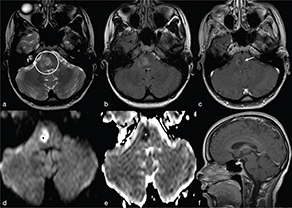

The abscess capsule is well-defined, smooth and complete. It shows a layered aspect, hypointense on FLAIR/T2-wi and hyperintense on T1-wi. The presence of collagen fibres and macrophages releasing free radicals are considered responsible for the short T1 and T2 of the rim due to their paramagnetic effect (Figure 2).7 The external low-signal rims on T2-wi could be useful to distinguish abscess from glioblastomas: in this case the rims, irregular or incomplete in the majority of cases, result from the store of haemorrhagic products surrounding the outer layer of the necrotic core.8

FIG 2. Nocardia Abscess in a 64-Year-Old Immunocompromised Man Presenting with Headache. A round lesion with thick capsule hyperintense on T1w (a) and hypointense on T2w/FLAIR-T2w (b–c) is shown. The lesion is characterised by a core of restricted diffusion (d–e). Typical ring-enhancement is present after intra-venous Gd administration; the coronal scan also reveals the presence of multiple lesions (f). A discreet amount of perilesional vasogenic oedema is present too (a–e).